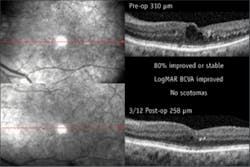

The study was designed to run for 12 months, with patient follow-up at three, six, and 12 months post-op. The results at three months showed that central macular thickness, as measured with optical coherence tomography (OCT), decreased by more than 5% in 16 patients (55% of eyes; see figure). It remained stable in seven patients (24% of eyes) and showed an increase in thickness in only 20% of eyes (six patients). A majority of the patients experienced an improvement in visual acuity. Microperimetry confirmed this increase in visual function in the majority of treated eyes and no evidence of laser damage to the photoreceptor cells in any of the eyes.

The OCT system used was the Spectral OCT/SLO produced by Ophthalmic Technologies Inc. (OTI, now a division of OPKO; Miami, FL), which contains a microperimetry option to assess the visual function of the retina and fovea as it relates to structural changes. The microperimetry runs simultaneously with the scanning-laser ophthalmascope and provides real-time tracking of retina movement and patient fixation.